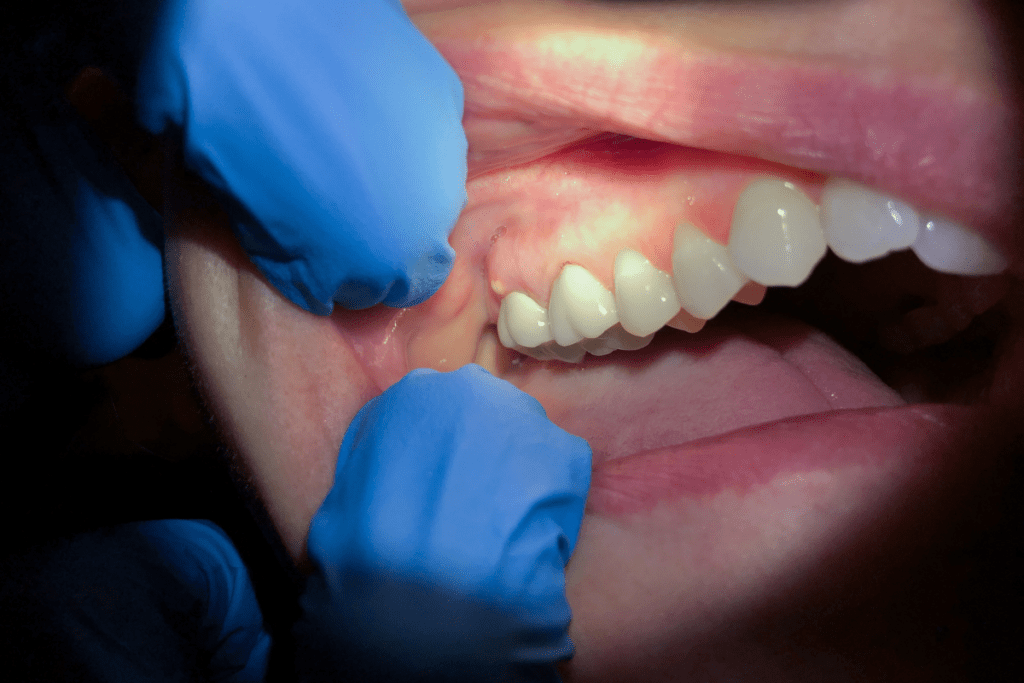

Visible Signs & Symptoms

Pain reaches a new level at stage 3 – often described as unbearable, constant throbbing that worsens when you lie down or bite down. Swelling appears in your face, jaw, or neck as the infection triggers an inflammatory response. You may notice a small, pimple-like bump on your gums (this is the abscess attempting to drain). Bad breath and a foul taste in your mouth are common, along with difficulty chewing, swallowing, or difficulty opening your mouth fully. Some patients develop a low-grade fever. At this stage, ignoring the problem is no longer an option.

Red Flag Symptoms (Stage 3)

Now the signs are unmistakable. Sharp, throbbing pain keeps you awake. Your face or jaw shows visible swelling. You notice a pimple-like bump on your gum, possibly with drainage. Don’t try managing this with painkillers alone. Call us immediately – this is urgent but not yet life-threatening. We can often save your tooth if you act now.